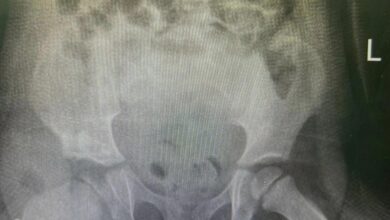

إنهاء معاناة طفلة مصابة بخلع ورك تخلقي بالخبر

أحوال – متابعات – إبتسام عشان : أنهى الفريق الطبي في مستشفى الملك فهد الجامعي بالخبر، التابع لجامعة الإمام عبد الرحمن بن فيصل معاناة طفلة مصابة بخلع ورك تخلقي. وأوضح…